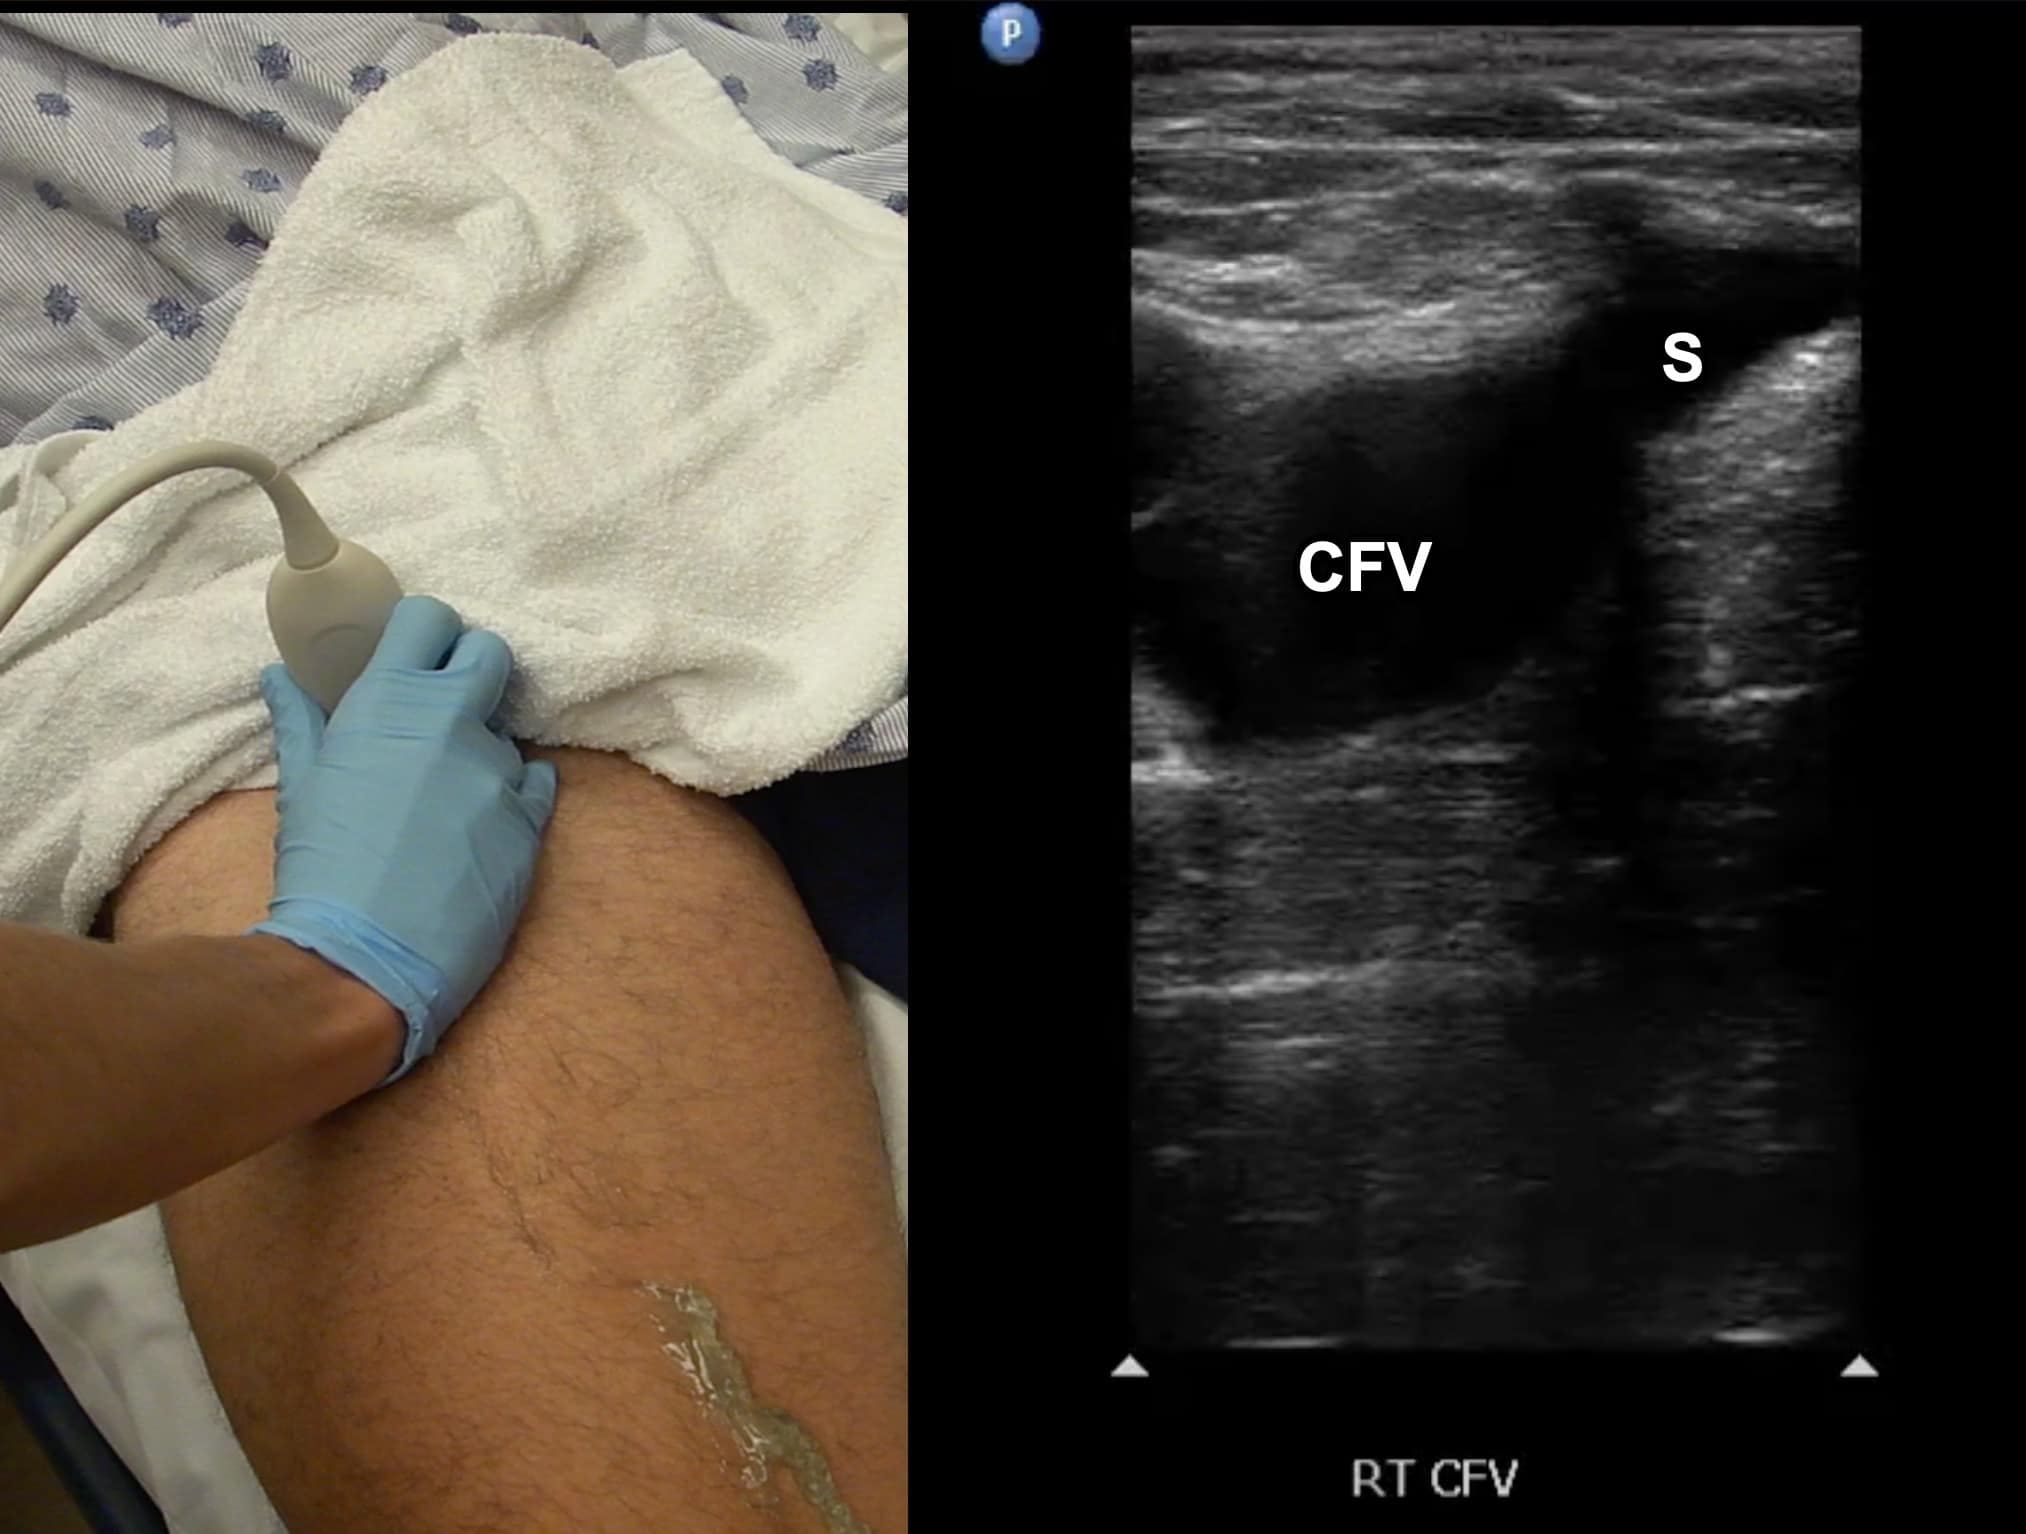

Due to its location in the pelvis, the EIV can be difficult to visualize, so the proximal protocol begins with the transducer in the transverse position high in the groin, just distal to the inguinal ligament with the CFV at the saphenous vein (SV) branch point visualized (Figure 3). A normal vein will be anechoic and easily compressible (Figure 4). Compression should be performed with the transducer transverse to the vein with compression being directed in an anterior-posterior direction. Compression should not be performed in a longitudinal plane to the vein since false-positive results can occur from “side-walling” and sliding off the vein, which can appear sonographically as a true compression. Tenting of the artery means that more than enough pressure has been applied.

Figure 3. Split screen demonstrating transverse window of common femoral vein (CFV)/greater saphenous vein (S) junction with transducer position (indicator toward patient’s right).